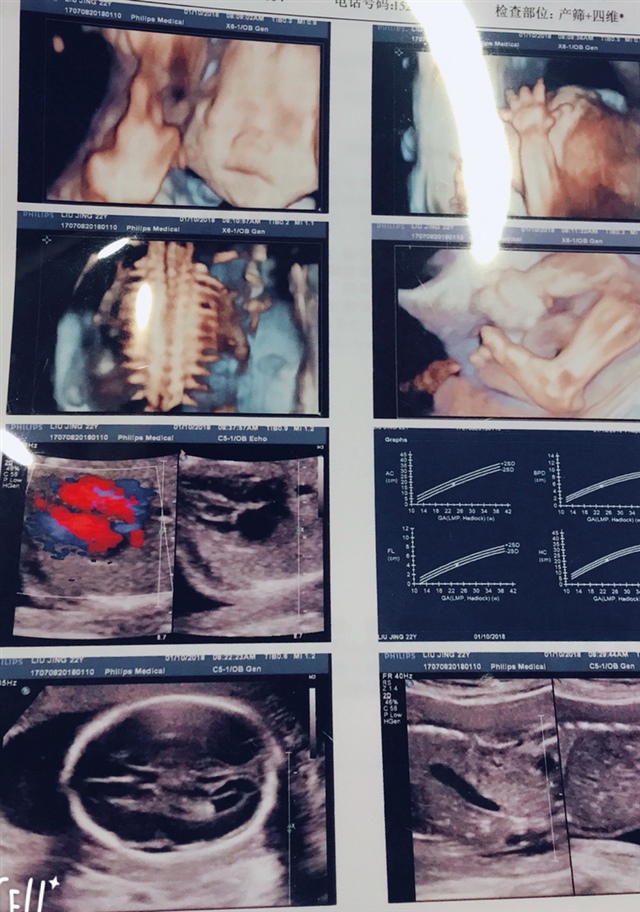

宝宝3个月8天

孕20周+3天

孕14周+1天

孕14周+6天

宝宝5个月21天

哇,好清楚啊

京京🌺凯丽

宝宝2个月11天